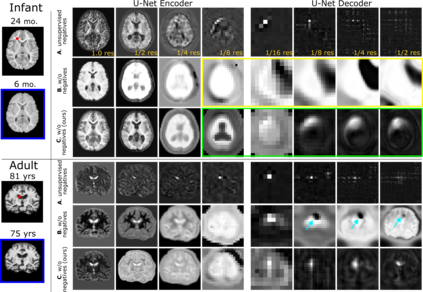

Recent self-supervised advances in medical computer vision exploit global and local anatomical self-similarity for pretraining prior to downstream tasks such as segmentation. However, current methods assume i.i.d. image acquisition, which is invalid in clinical study designs where follow-up longitudinal scans track subject-specific temporal changes. Further, existing self-supervised methods for medically-relevant image-to-image architectures exploit only spatial or temporal self-similarity and only do so via a loss applied at a single image-scale, with naive multi-scale spatiotemporal extensions collapsing to degenerate solutions. To these ends, this paper makes two contributions: (1) It presents a local and multi-scale spatiotemporal representation learning method for image-to-image architectures trained on longitudinal images. It exploits the spatiotemporal self-similarity of learned multi-scale intra-subject features for pretraining and develops several feature-wise regularizations that avoid collapsed identity representations; (2) During finetuning, it proposes a surprisingly simple self-supervised segmentation consistency regularization to exploit intra-subject correlation. Benchmarked in the one-shot segmentation setting, the proposed framework outperforms both well-tuned randomly-initialized baselines and current self-supervised techniques designed for both i.i.d. and longitudinal datasets. These improvements are demonstrated across both longitudinal neurodegenerative adult MRI and developing infant brain MRI and yield both higher performance and longitudinal consistency.